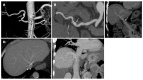

Orthotopic liver transplantation (OLT) represents a major treatment for end-stage chronic liver disease, as well as selected cases of hepatocellular carcinoma and acute liver failure. The ever-increasing development of imaging modalities significantly contributed, over the last decades, to the management of recipients both in the pre-operative and post-operative period, thus impacting on graft and patients survival. When properly used, imaging modalities such as ultrasound, multidetector computed tomography, magnetic resonance imaging (MRI) and procedures of direct cholangiography are capable to provide rapid and reliable recognition and treatment of vascular and biliary complications occurring after OLT. Less defined is the role for imaging in assessing primary graft dysfunction (including rejection) or chronic allograft disease after OLT, e.g., hepatitis C virus (HCV) recurrence. This paper: (1) describes specific characteristic of the above imaging modalities and the rationale for their use in clinical practice; (2) illustrates main imaging findings related to post-OLT complications in adult patients; and (3) reviews future perspectives emerging in the surveillance of recipients with HCV recurrence, with special emphasis on MRI.